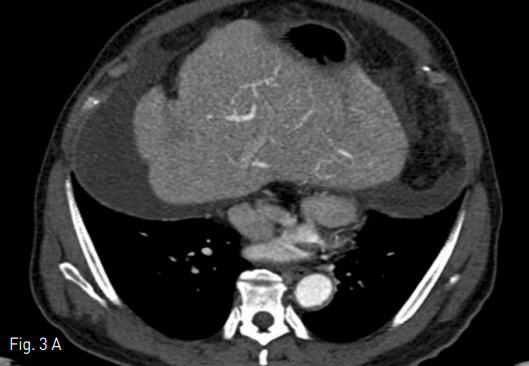

Fig 2

Indirect portography was obtained during the venous phase following iodinated contrast medium injections in the superior mesenteric artery (SMA). Digital subtraction image of portography showed that the diameter of the right portal vein was much smaller than that of the left portal vein.